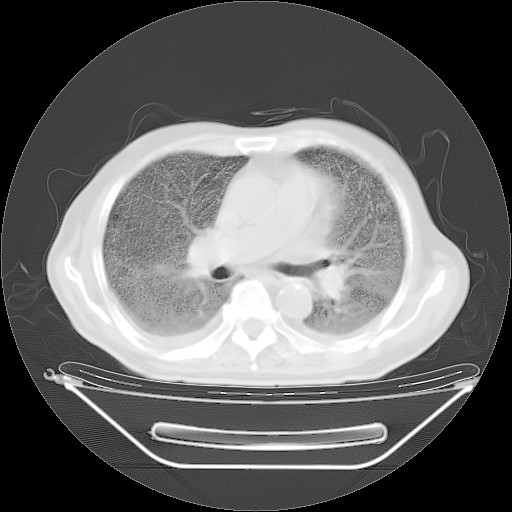

今天复查肺部CT,发现双肺广泛磨玻璃样改变。所以我把3月19日和5月9日相隔50天的肺部CT上传。请大家会诊。

5月9日肺部CT(在4月27日齐鲁医院肺部CT描述部分肺组织磨玻璃样改变,12天后肺组织广泛磨玻璃样改变)

大致读了系列胸部CT:纵隔窗无明显异常,肺窗:从4、27至今:主要是双肺中下野外带可见毛玻璃样改变,目前处于急性肺泡炎阶段,至于原因考虑1、结替组织或胶原血管性疾病所致?2、恶性疾病如恶组在肺部所致的表现或细支气管肺泡癌?3、药物或其它原因如肺蛋白沉着症所致肺泡炎目前不太可能?总之,明天就去请我院的呼吸科、感染科、血液科和临免专家会诊哈。